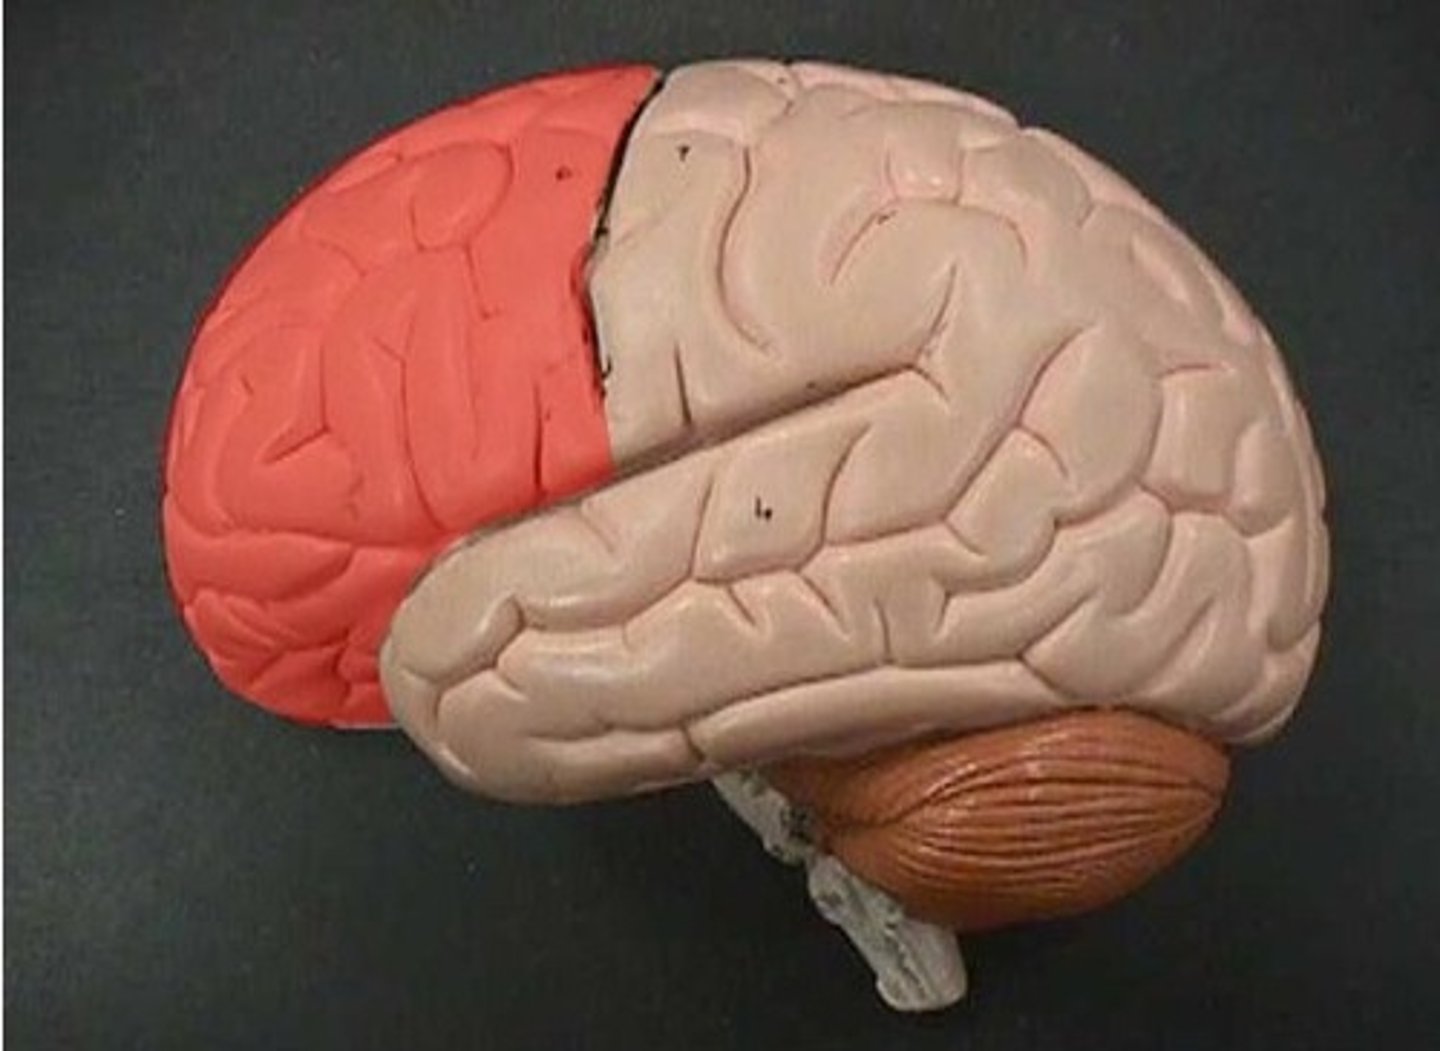

Frontal lobe

speaking, motor movement, judgement, and decision making